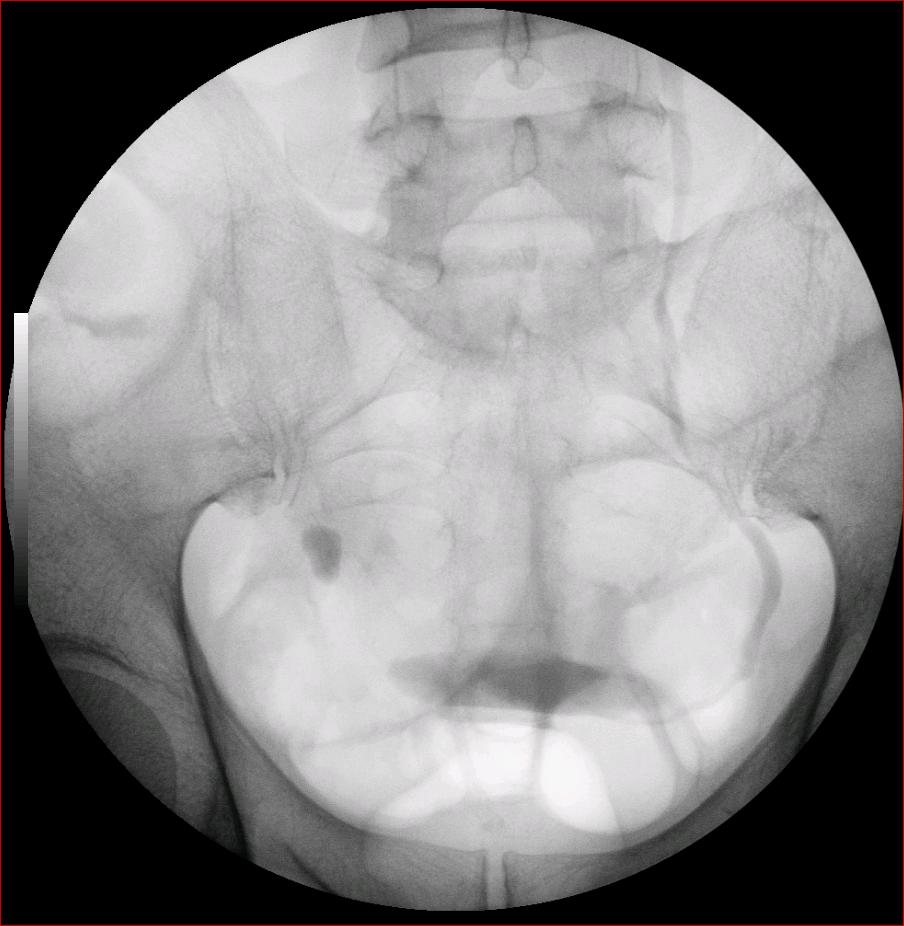

以下是引用luoxinjun在2008-2-18 15:54:00的发言:[br]右肾积水,右输尿管下端结石

以下是引用zhangxiangjun在2008-2-18 21:01:00的发言:[br]右输尿管盆段末端结石,继发其近端输尿管、右肾积水。

以下是引用hexue在2008-2-18 17:33:00的发言:[br]右输尿管下段结石并右肾及右输尿管积水扩张

以下是引用杀毒软件在2008-2-18 16:24:00的发言:[br]右输尿管下段结石,肾盂积水。